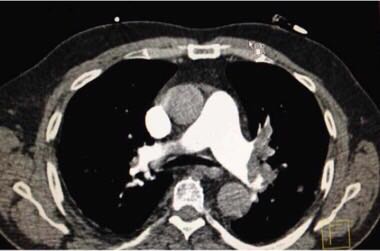

64岁女性,突发胸痛、呼吸困难3小时。既往房颤病史多年,未抗凝治疗。胸部CT扫描如图。什么诊断?下一步如何治疗?